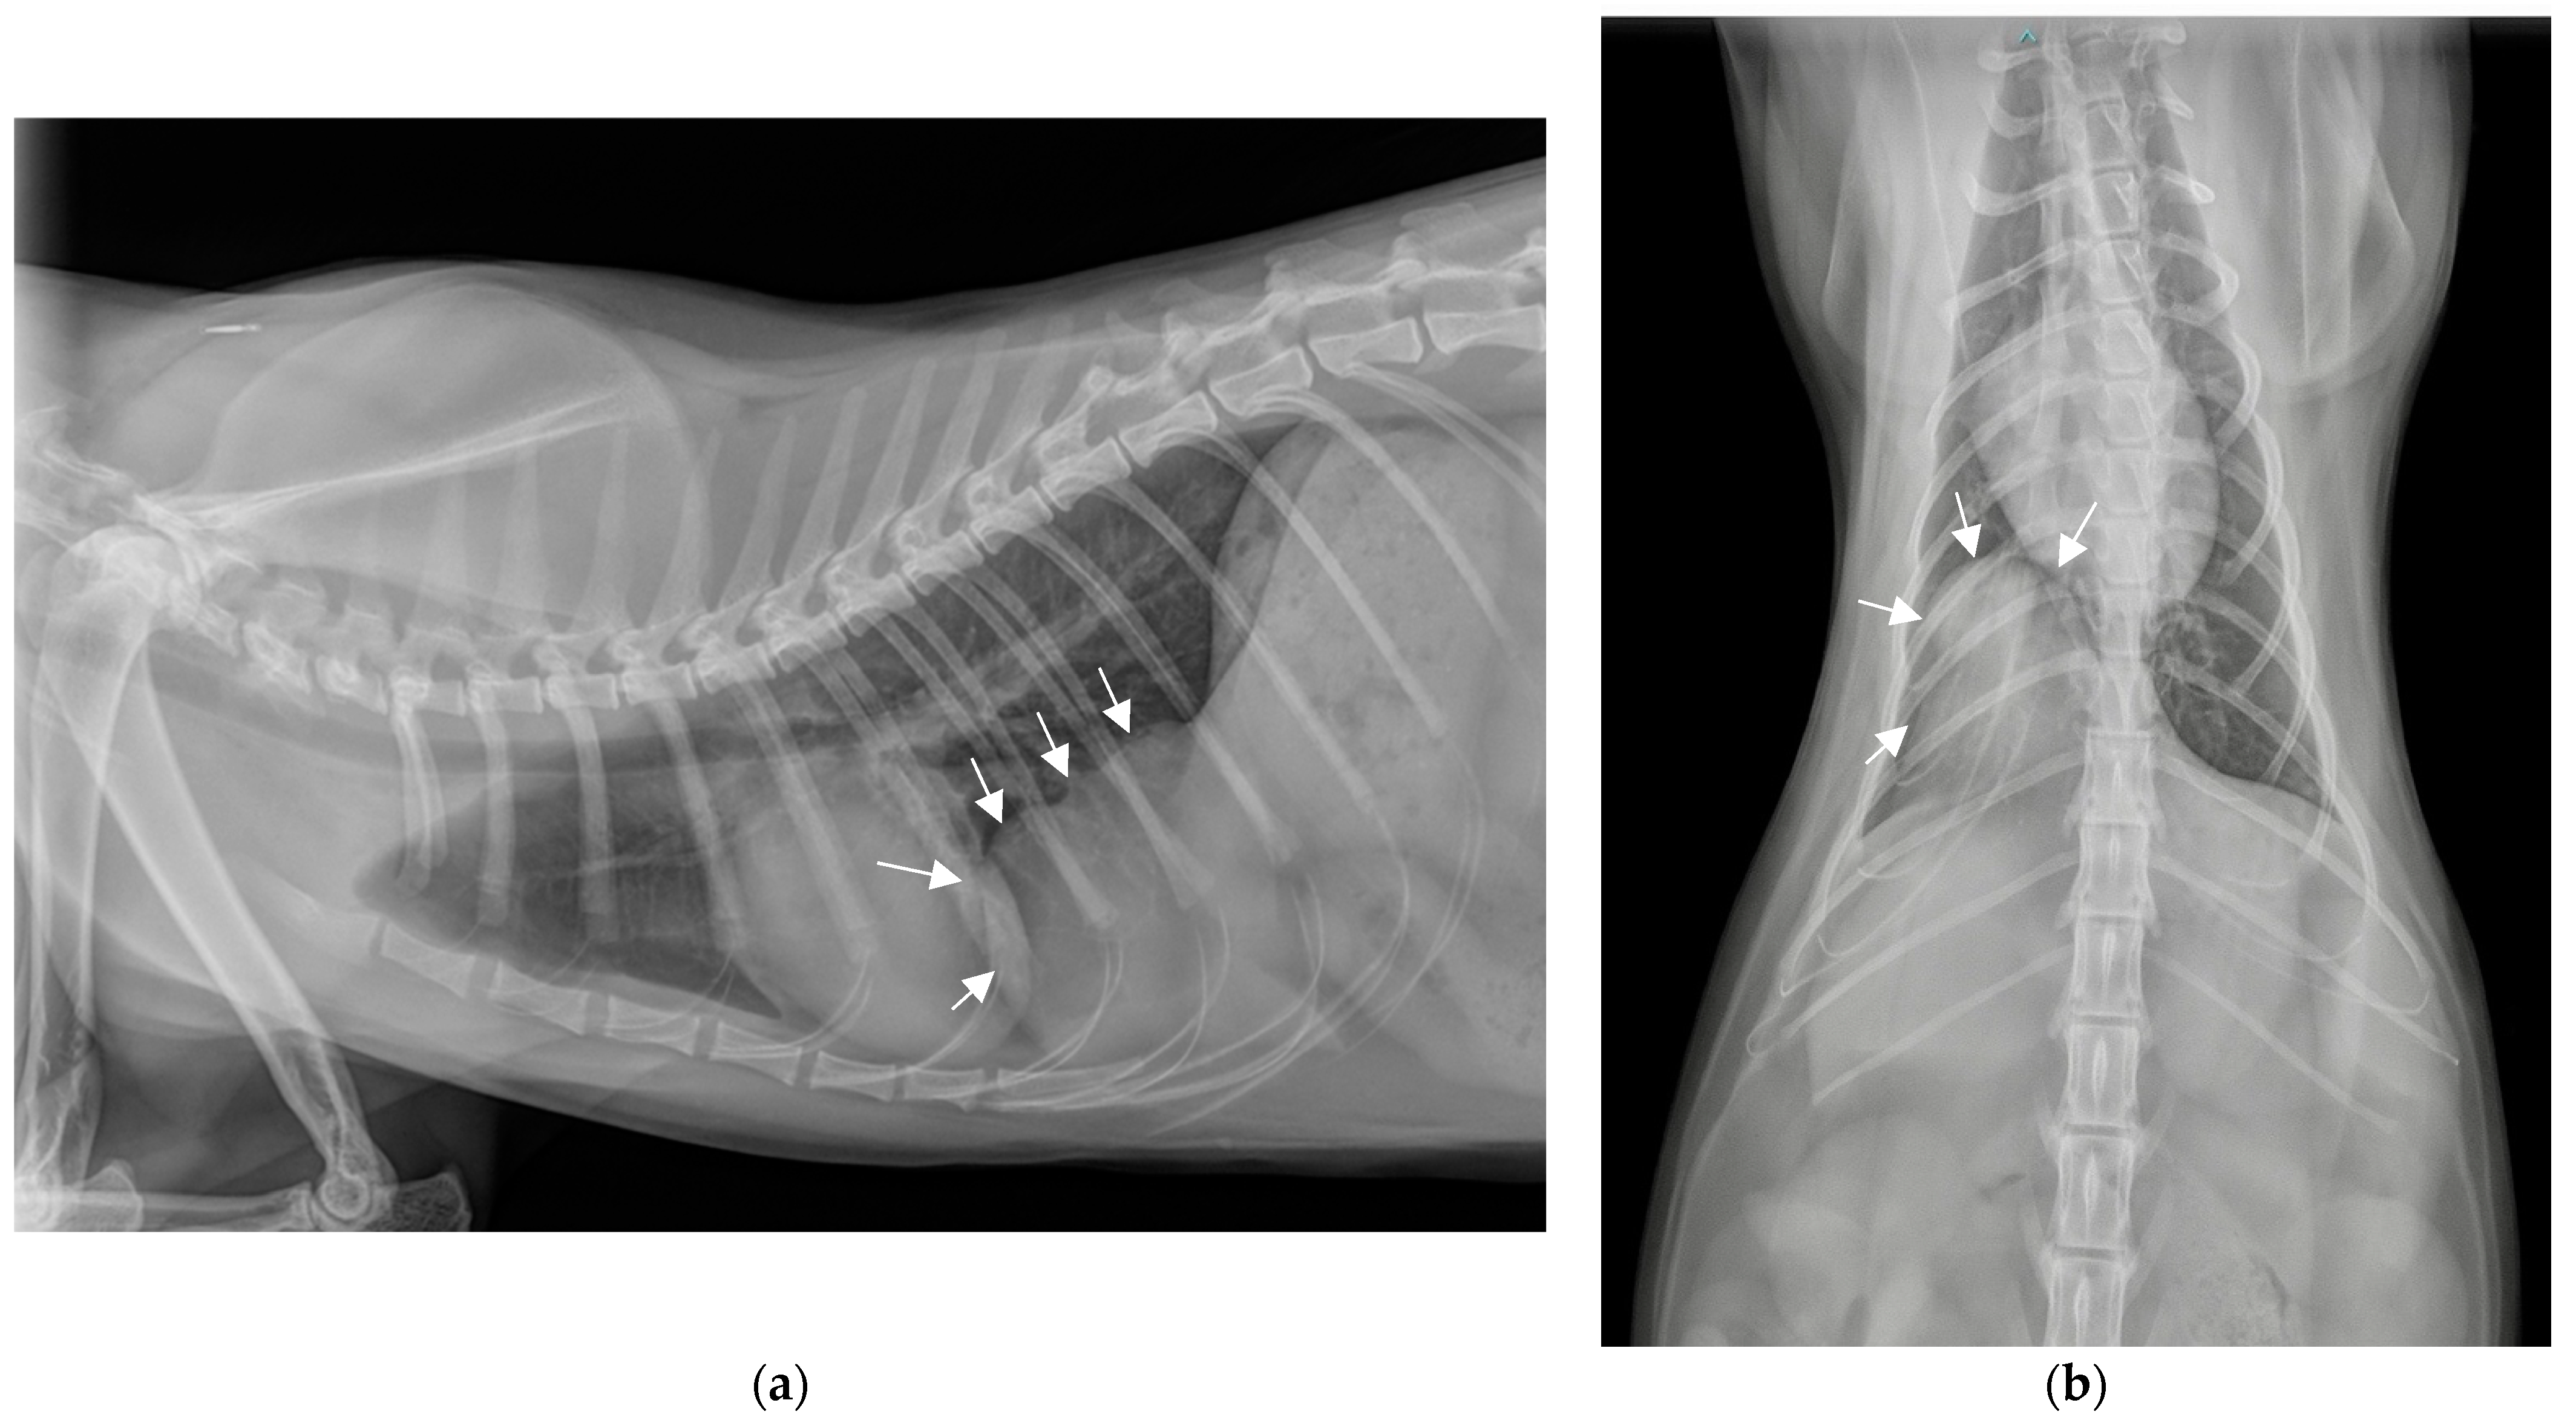

2.2. Additional Tests

2.3. Diagnosis